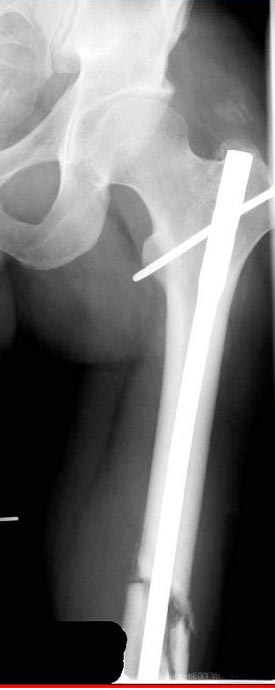

Операцию провели в два этапа, сперва удалили штифт, рассверливание римером на пару мм большего диаметра, определение чувствительности на анаэробную и аэробную культуру (где исследования показали негативный результат чувствительности), через дней десять - начали аппаратную фиксацию.

Гвоздь для ротационных смещениц был бы идеальнымимплантом, после коррекции есть возможность блокировать, но из-за укорочения метод оставил на последнее место. Есть метод Сhaplan лечения ложных суставов бедра, где необходимость bone graft, накладывается феморальный дистрактор и после удаления штифта - рассверливание, через проксимальный канал вводят костный графт в место ложного сустава под рентген контролем, потом вводят штифт, кстати, само рассверливание дейстивует как стимулятор - активизирует восстановительный процесс.

Обычный мой первый выбор - вариант с пластиной, - учитывая бывшую инфекцию, открытую травму, посчитал метод менее приемливым.

Еще больной был противв костной аутопластики, да и самому тоже хотелось перейти к истокам "откуда мы" более усовершенствованному Курганскому методу.